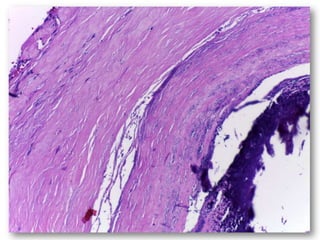

Uma mulher de 72 anos apresentou um nódulo assintomático na mucosa labial inferior há cerca de três meses. Após biópsia, o diagnóstico foi de flebólito, descartando as hipóteses iniciais de miofibroma ou neurofibroma.